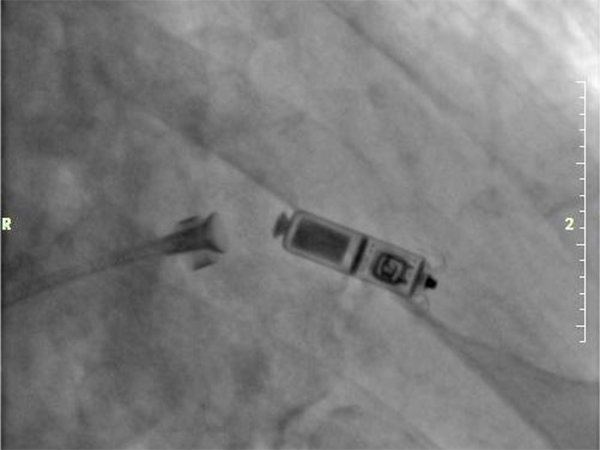

手術在科主任梁田帶領下,電生理團隊劉敏主任、盧磊主任共同上臺完成。在局部麻醉下,通過股靜脈穿刺,將起搏器通過導管植入到心腔內部,術中Micra AV無導線起搏器僅一次釋放即成功,釋放位置精準,手術全程時間約40分鐘,患者術后反應良好,6小時后即可下床走動。

1. 體重更輕、體積更小。大小似一粒維生素膠囊,體積約1.0cm3(相較于傳統(tǒng)起搏器減小了93%),長度為2.59cm,重量僅有1.75g。